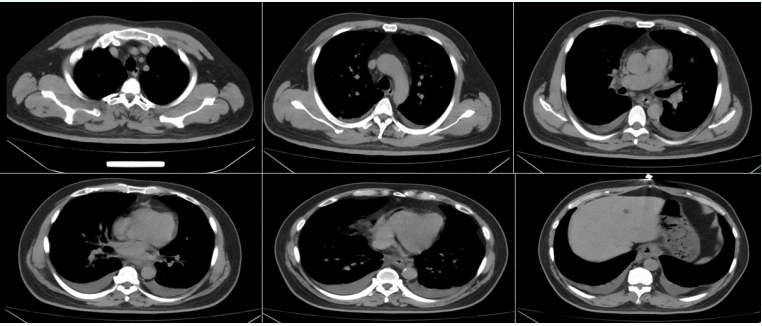

• 外院胸部CT(2024-07-11):两肺弥漫斑片状模糊影,双侧少量胸腔积液(图16)

16  患者外院胸部CT(2024-07-11)